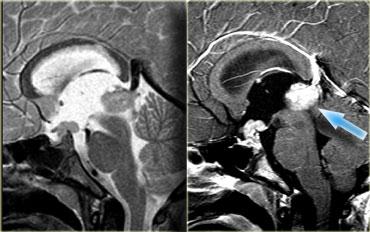

U Tuyến Yên Đại Tuyến (Macroadenoma)

Theo định nghĩa, u tuyến yên đại tuyến (macroadenoma) là các u tuyến có kích thước trên 10mm.

Chúng thường là các tổn thương đặc, mềm, thường có các vùng hoại tử hoặc xuất huyết khi kích thước tăng lên.

Khi phát triển, u trước tiên làm giãn rộng hố yên (sella turcica) rồi sau đó phát triển lên trên.

Trong ví dụ về u tuyến yên đại tuyến này, có sự lan rộng lên vùng trên yên (suprasellar) với sự đẩy lên và chèn ép giao thoa thị giác.

Do là các khối u mềm, chúng thường bị thắt lại tại màng hoành yên (diaphragma sellae), tạo nên hình ảnh ‘người tuyết’ đặc trưng.

Đây là một đặc điểm giúp phân biệt u tuyến yên đại tuyến với u màng não (meningioma).

Một đặc điểm khác có thể giúp phân biệt là sự giãn rộng của hố yên – điều này thường chỉ xảy ra với u tuyến yên đại tuyến có nguồn gốc từ trong hố yên.

Bên trái là một ví dụ khác về u tuyến yên đại tuyến.

Tổn thương bắt đầu từ hố yên, vốn đã bị giãn rộng, và lan rộng vào bể dịch não tủy trên yên (suprasellar cistern).

Lưu ý hình ảnh ‘người tuyết’ kinh điển được tạo ra do sự thắt nghẽn bởi màng hoành yên.

Chú ý mức dịch-máu (blood-fluid level), cho thấy có xuất huyết.

Tầm quan trọng của việc quan sát hướng nghiêng của các lá màng hoành yên đã được đề cập trước đó.

Trên các hình ảnh chuỗi xung T2W bên phải, có thể thấy các lá màng hoành bị đẩy lên trên bởi khối u đại tuyến này, vốn bắt đầu từ hố yên và đang phát triển lên trên.

Một tổn thương có nguồn gốc từ phía trên hố yên và phát triển xuống dưới sẽ đẩy các lá màng hoành theo hướng ngược lại (điều này có thể thấy trong trường hợp u màng não chẳng hạn).